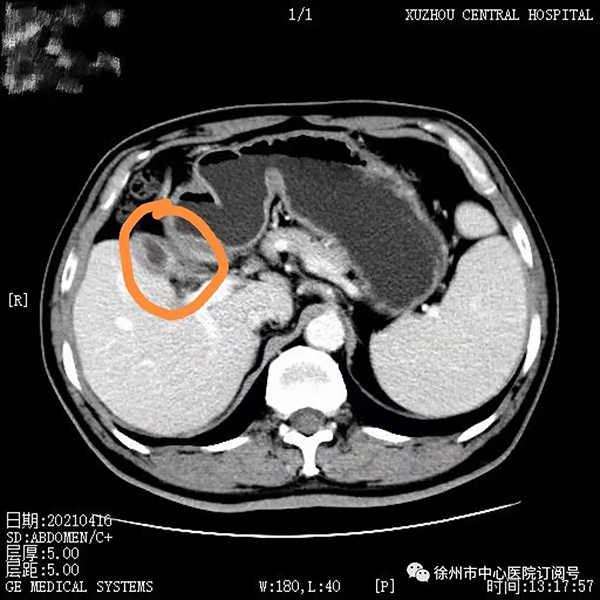

2020年8月,董先生行第一次靶免治療,無特殊不良反應(yīng),后間隔21天行一次治療至第4療程;2020年10月腹部CT檢查見腫瘤較前縮小,病情持續(xù)好轉(zhuǎn);2021年4月進(jìn)行第9療程再次復(fù)查腹部CT顯示,此時(shí)腫瘤較第一次治療時(shí)已明顯縮小。

2021年4月,第9療程腹部增強(qiáng)CT:膽囊癌復(fù)查,膽囊壁增厚毛糙,較之前無明顯變化。